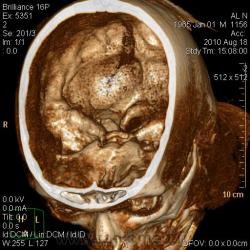

Неубедительно, поверхность височной доли в базальных отделах "заворачивается" медиально, поэтому срез идет наискосок к гематоме, и она выглядит шире (как на макушке). Вы посмотрите это же место на фронтальной реконструкции, возможно это будет уже не эллипс.

Качество изображения не высокое. Поэтому попробую продемонстрировать кадр, где, на мой взгляд, есть эллипс-линза в височной доле, подтверждающая "эпидуральность". Несомненно, преобладает субдуральная гематома.

На фронтальной и получается то серп, то эллипс. Только сейчас под рукой нет.